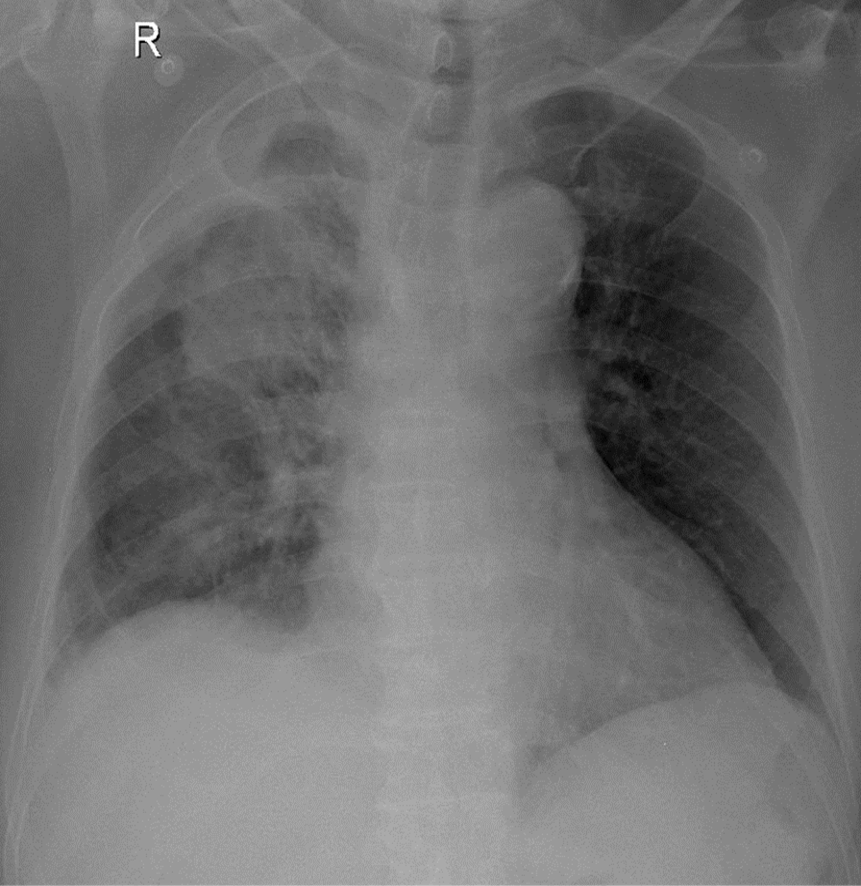

1-Thâm nhiểm phế nang lan tỏa phổi (P) => Viêm phổi 2-U thùy trên phổi (P) 3-Tràn dịch màng phổi (P) khu trú vùng đỉnh 4-Cung động mạch chủ đóng vôi